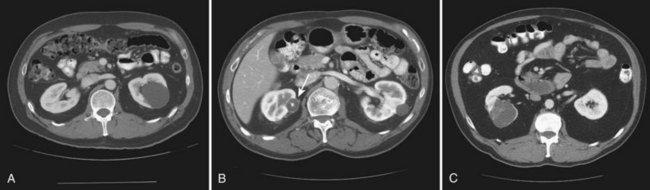

The greatest clinical dilemma remains the inability to confidently differentiate between renal oncocytoma and RCC on clinical or radiographic testing. Both have a similar age at presentation, have a male-to-female predominance, and are similarly sized at presentation. Although oncocytomas were more likely to be asymptomatic at presentation, most RCC are also diagnosed incidentally in the current era, eliminating this clinical scenario as a differentiator (Davis et al, 1991; Licht et al, 1993; Lieber, 1993; Amin et al, 1997; Perez-Ordonez et al, 1997; Dechet et al, 1999). The typical spoke-wheel pattern seen on angiography or the stellate scar on cross-sectional imaging may bring up the question of a renal oncocytoma, but these findings have a poor predictive value by themselves (Davidson et al, 1993; Licht et al, 1993; Licht, 1995). On MRI, oncocytomas may have distinct T1 and T2 signal patterns that can be suggestive but these are not definitive findings (Harmon et al, 1996). T2-weighted images on MRI do not differentiate oncocytoma from RCC (Dann et al, 2006). For lesions undergoing surveillance, the growth rates of RCC and oncocytoma are similar, so growth kinetics also do not help differentiate these tumors either (Chawla et al, 2006; Crispen and Uzzo, 2007; Siu et al, 2007). In 4% to 13% of cases, tumors are multicentric, are bilateral, or have a metachronous presentation (Lieber et al, 1987; Davis et al, 1991; Licht et al, 1993; Amin et al, 1997; Perez-Ordonez et al, 1997; Dechet et al, 1999; Tickoo et al, 1999; Minor et al, 2003). Familial renal oncocytomatosis was initially described (Weirich et al, 1998) in five families in which it presented at a young age as multicentric, bilateral and recurrent oncocytomas. Nonfamilial forms of bilateral multifocal oncocytomas resembling oncocytomatosis can also occur (Fig. 51–6). A recent cytogenetic evaluation of a patient with apparently sporadic oncocytomatosis and hybrid tumors showed different chromosomal losses than the Birt-Hogg-Dubé syndrome (Al-Saleem et al, 2004).

Recent clinical studies highlight the differing incidence of oncocytoma based on age and gender. Cao and colleagues (2005) and Skolarus and colleagues (2008) showed an increasing incidence of oncocytoma in older patients presenting with a small incidentally discovered renal mass. Two different reports highlight that younger females are nearly twice as likely as their male counterparts to have a benign tumor, which includes oncocytoma and angiomyolipoma but is probably largely driven by the higher rates of angiomyolipoma in women (Cao et al, 2005; Snyder et al, 2006).